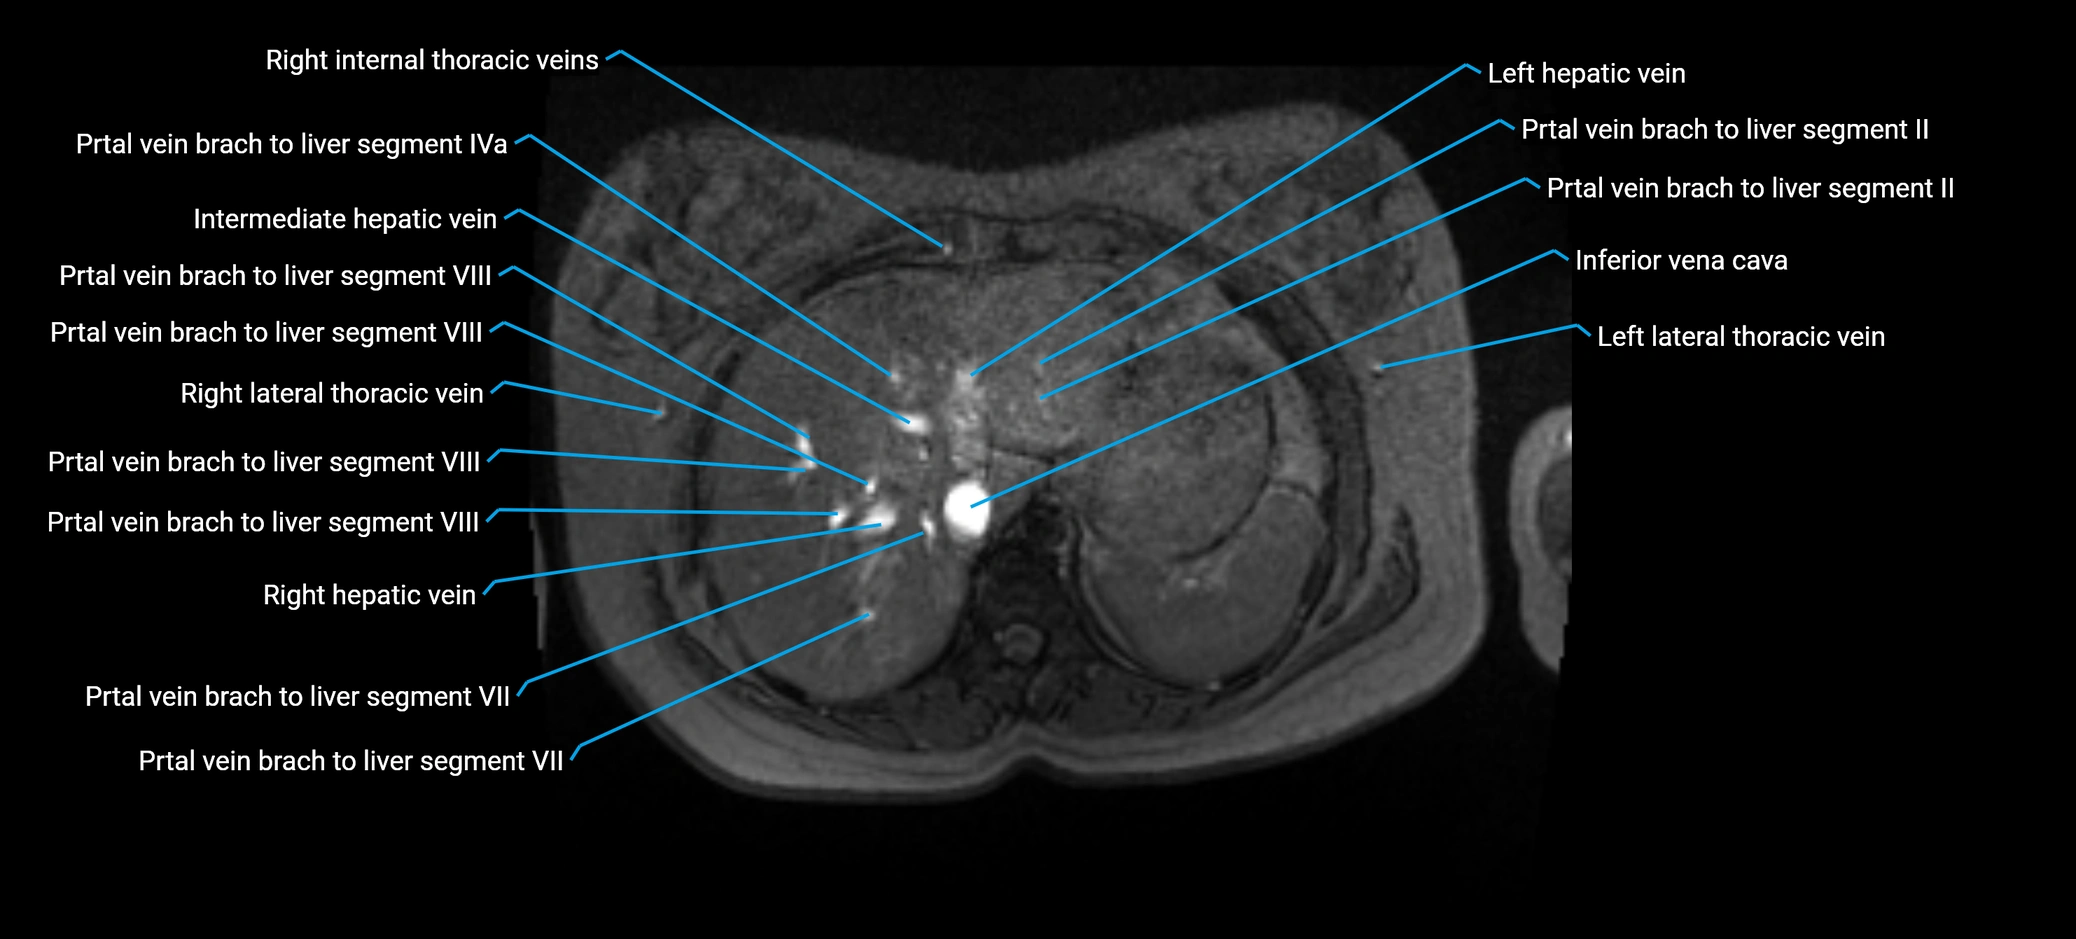

MRI image

image